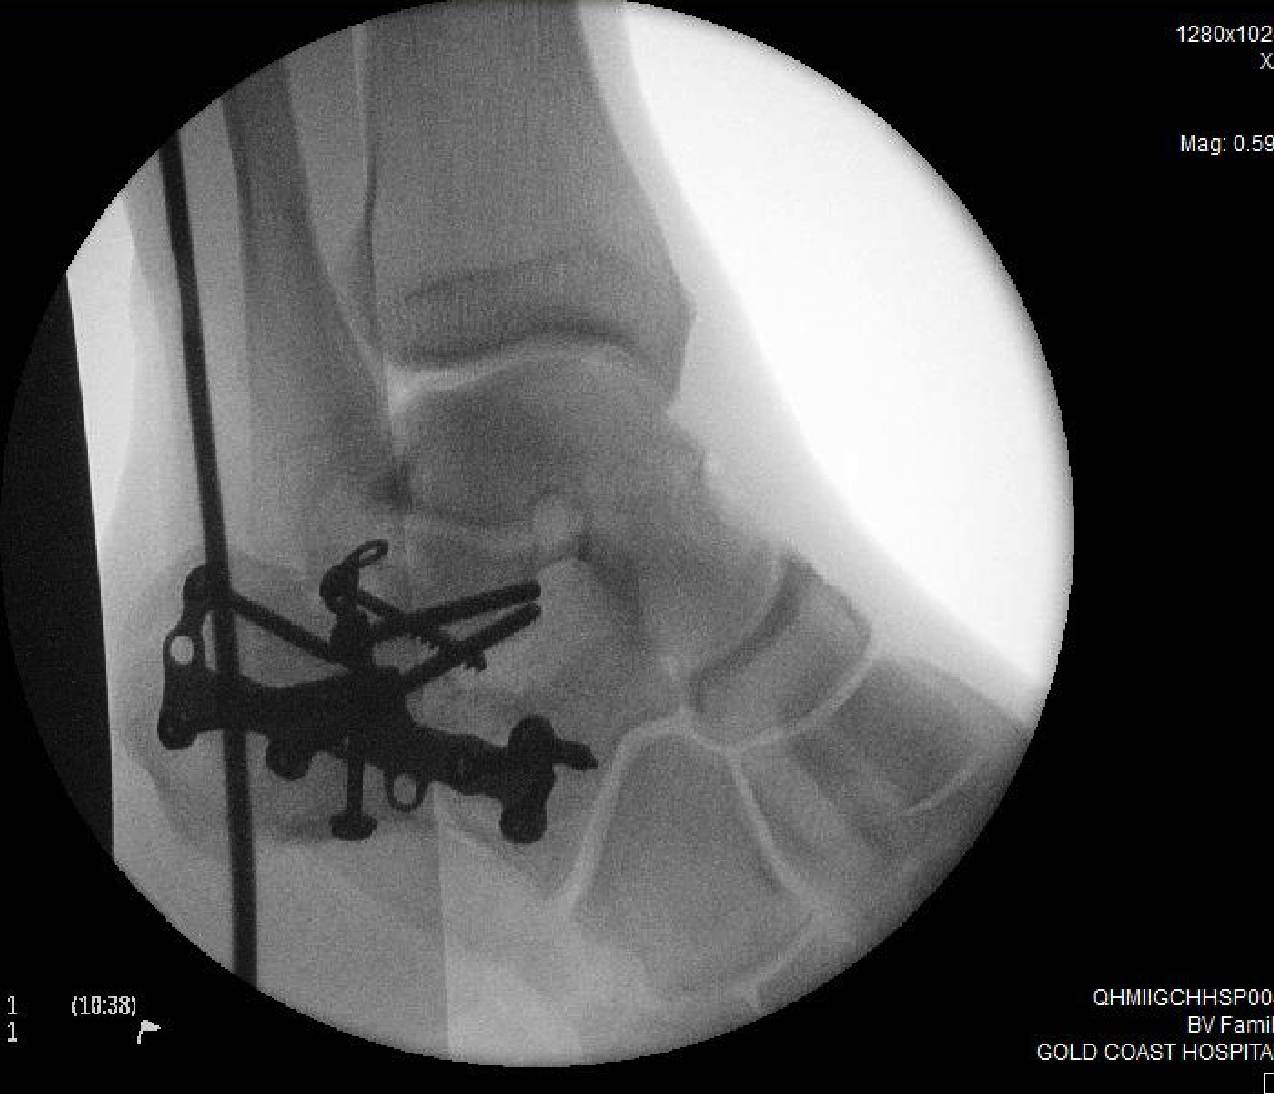

Warning!! Don't jump in shallow water